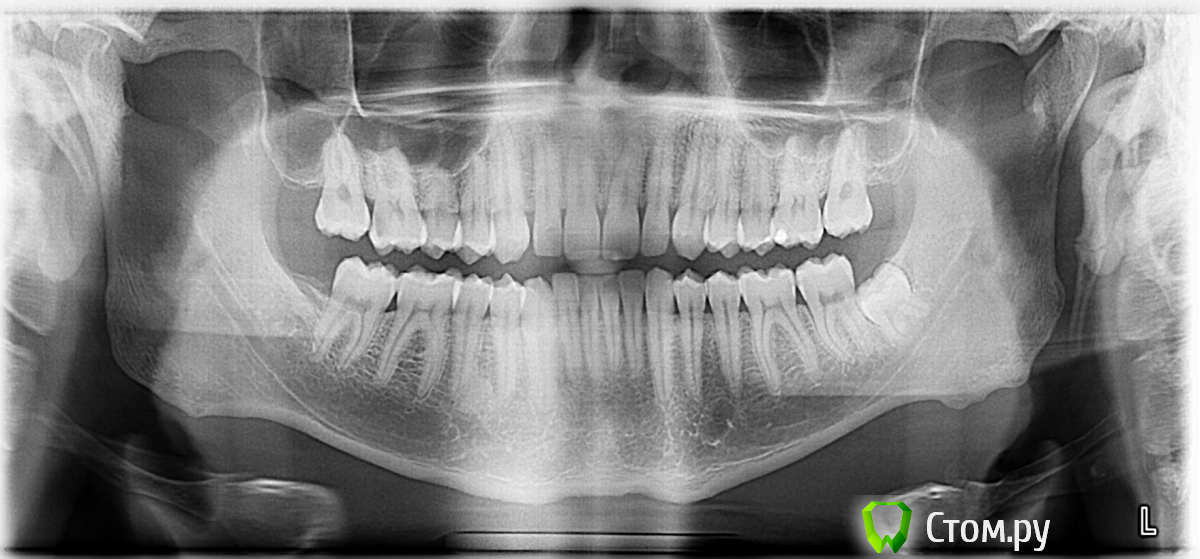

Padrezzz Опубликовано 11 июня, 2014 Поделиться Опубликовано 11 июня, 2014 (изменено) Полгода назад я получил удар в подбородок локтём с размаха. После этого что-то клацнуло пару раз в щеке слева (на уровне рта-носа) и затихло. И вот без какой-либо причины уже 2 недели как начался кошмар...Чтобы открыть рот полностью, я должен сместить челюсть ВПРАВО и получить сильный щелчок СЛЕВА (в левой щеке на уровне рта/ноздрей носа) + неприродно увеличилась какая-то мышца возле скулы СЛЕВА + несколько раз конкретно закладывало оба уха на длительное время. Судя по смещению центра нижних зубов при открытии рта нижняя челюсть уходит ВЛЕВО.Пару раз при резком открытии на всю (без предварительного смещения) был слышен сильный трекс в районе ближе к области между ухом и глазом СЛЕВА и после чувствовался привкус крови, но в слюне крови не обнаружил... Сначала был у травматолога, но безрезультатно. Потом обращался в 2 челюстно-лицевых центра и к 2ум просто хирургам-стоматологам. О заведующих центров, их тяге к наживе и наплевательскому отношению к пациенту я промолчу. О советах хирургов типа "жуйте прищепку и прикладывайте димексид", тоже... В итоге я не получил абсолютно никаких адекватных ответов, кроме фразы "скорей всего артрит сустава" и "это не лечится". В итоге я попал через знакомых к стоматологу, которая якобы сталкивалась с этой проблемой и знает, что делать. Она без объяснений сразу же сделала мне ИЗБИРАТЕЛЬНОЕ ПРИШЛИФОВЫВАНИЕ ПО КОПИРКЕ (по 2 боковых зуба с обеих сторон, спиливала и снизу и по бокам) !!! Мне 29 лет и у меня всего 1 пломба за всю жизнь. Никаких зубов не удаляли.Ещё сказала, что нужно заказывать КАППУ иностранного производства (универсальную, а НЕ индивидуальную под мои зубы) и носить её в течении года, одевая по ночам и якобы будет мне счастье.Также она посоветовала не смещать челюсть и не производить щелчки, а открывать рот насколько это возможно без сдвигов. Я так и делал в течении 3 дней. В итоге теперь я не могу вообще ей двигать не вправо, ни в лево ни на милиметр и открывать полностью - стала зацеплена намертво и щелчок сделать просто не получается... Открывается на уровень зубной щетки.Но вроде как увеличенная мышца хоть немного уменьшилась после пришлифовки... В связи с этим у меня вопрос:1) Можно ли было проводить избирательное пришлифовывание абсолютно здоровых зубов у человека без дефекта прикуса по копирке без слепка и диагностики ортодонта? И чем это может быть чревато?2) Каков, всё-таки, диагноз и что мне делать, к кому обращаться?3) К чему может привести данное заболевание в будущем, если оно не будет вылечено? К вопросу прикрепляю свои снимки, которые никто даже толком не смотрел, а если и смотрел, то "как баран на новые ворота"... Так и не понял, зачем меня посылали их делать...Снимки делались ДО пришлифовки зубов!P.S. Проводили проверку, пальпацию скрытого зуба мудрости - не беспокоит, сказали он ни при чём. Очень прошу - помогите разобраться во всём этом!!! Заранее благодарю за ответы!!! !!!ПОМОГИТЕ!!! Изменено 11 июня, 2014 пользователем Padrezzz Ссылка на комментарий

Skip Опубликовано 12 июня, 2014 Поделиться Опубликовано 12 июня, 2014 Так у Вас там ещё мегастилоид 2-го типа, батенька: http://i6.pixs.ru/storage/8/3/5/post391320_2142137_12522835.png Ощущение инородного тела или что-то вроде этого в горле никогда не чувствовали..? Остальные снимки не информативные, можно выбросить... 1) Можно ли было проводить избирательное пришлифовывание абсолютно здоровых зубов у человека без дефекта прикуса по копирке без слепка и диагностики ортодонта? И чем это может быть чревато? Категорически было нельзя! А чревато тем, что и произошло на 3- день... 2) Каков, всё-таки, диагноз и что мне делать, к кому обращаться? Судя пока только по Вашему рассказу - вывих суставного диска. На ОПТГ вроде бы не видно перелома суставного мыщелка и дай Бог, но мне хочется увидеть КТ Вашего черепа вместе с визуализацией в 3D. Поспрашивайте там у себя в Днепропетровске, наверняка где-то стоят такие томографы. Снимки должны быть, что-то вроде этого: http://i.pixs.ru/storage/8/9/2/ooa05133f1_9425665_12522892.jpg Удар в область подбородка, а значит симфизиса нижней челюсти, прямиком переносится в область суставных отростков. 3) К чему может привести данное заболевание в будущем, если оно не будет вылечено? Да тут много чего можно рассказать, поэтому проблему эту нужно как-то решать. Когда сустав ещё щёлкал, нужно было просто мануально вправить диск, на что уходит минуты. Затем изготовить КАПУ, но только индивидуальную репозиционирующую, а не иностранного производства. Неужели там хирургов толковых нет..? 2 Ссылка на комментарий

Padrezzz Опубликовано 18 июня, 2014 Автор Поделиться Опубликовано 18 июня, 2014 Специалиста нужно искать, который хорошо знает ВНЧС и окклюзию. Сегодня был у последнего спеца в области, пишущего диссертацию по внчс. Глядя на панорамный снимок, который я выложил в самом начале, он дал заключение, что проблема в следующем:- у меня левосторонняя форма жевания и немного неправильный прикус (головка сустава слева деформирована вследствие этого), - зуб мудрости давит на нижние зубы, смещая их, - главная причина щелчков и дискомфорта из-за СВЯЗОК сустава. Диагноз - артрит. По его мнению пришлифовывание снизило высоту прикуса, головки сустава поднялись выше и из-за этого я не могу теперь выдвигать нижнюю челюсть вперед и двигать по сторонам. С диагнозом мануальщика не согласен. Как и что мне там "вправили" конечно понятия не имеет. Рекомендации: удалить зуб мудрости, а через несколько месяцев уже можно делать слепок и проверять прикус и окклюзию и то, если я будучувствовать какой-то дискомфорт. А если нет, то значит организм сам пристроился к новым изменениям. Хотелось бы услышать Ваше мнение на этот счёт... Спасибо. Ссылка на комментарий